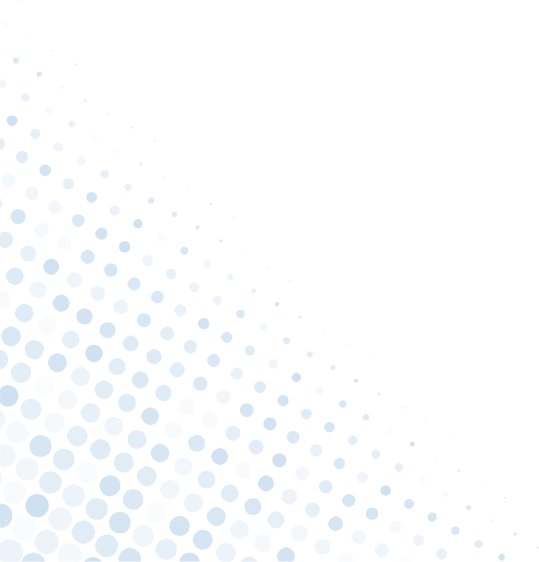

The Advantages of Arthroscopic Joint Surgery

In today's world, minimally invasive joint surgery is quickly becoming the preferred method for many orthopedic procedures. Arthroscopic surgery, also known as keyhole surgery or arthroscopy,

Benefits of Arthroscopic Surgery for Joint Injuries

Joint injuries can be debilitating, causing pain and limiting mobility. Whether resulting from sports-related accidents, degenerative conditions, or traumatic incidents,

An Overview of Minimally Invasive Joint Surgery Techniques

Joint pain and dysfunction can significantly impact a person's quality of life, making even simple tasks a challenge.When conservative treatments like physical therapy and medication fail to provide

The Benefits of Choosing an Arthroscopic Surgeon for Your Joint Health Needs

Arthroscopy is a minimally invasive surgical procedure used to diagnose and treat joint problems. For individuals experiencing joint pain or injury, selecting an arthroscopic surgeon

Advanced Treatment for Arthroscopy and Sports Medicine

For a sports person or an athlete, injuries mean a major disruption either in their career or routine. Be it a minor or major injury, it doesn’t take time for them to become an inconvenience.